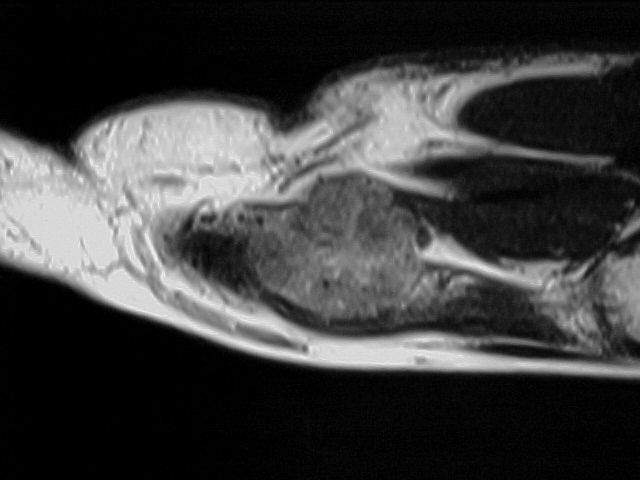

36y, male, Discrete pain and increase of volume between the 2nd and 3rd MCs

Case to follow the sent by Kyung, showing a glomus tumor in an unusual place

Glomus tumors